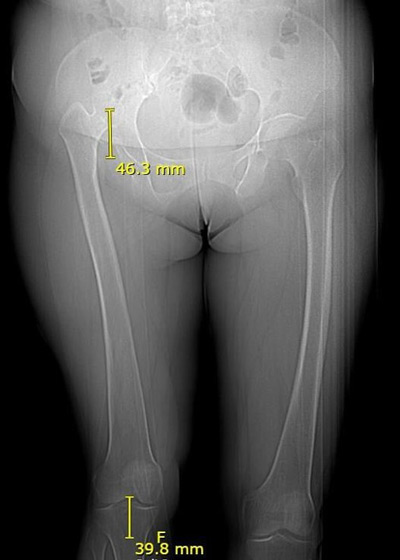

Pre-operative X-rays and CT-scan

Management of a hip dysplasia in a middle-aged woman: Pre-operative X-rays and CT-scan

• 60 year old lady

• Severe right hip pain since 1 year

• ✔️Crowe IV